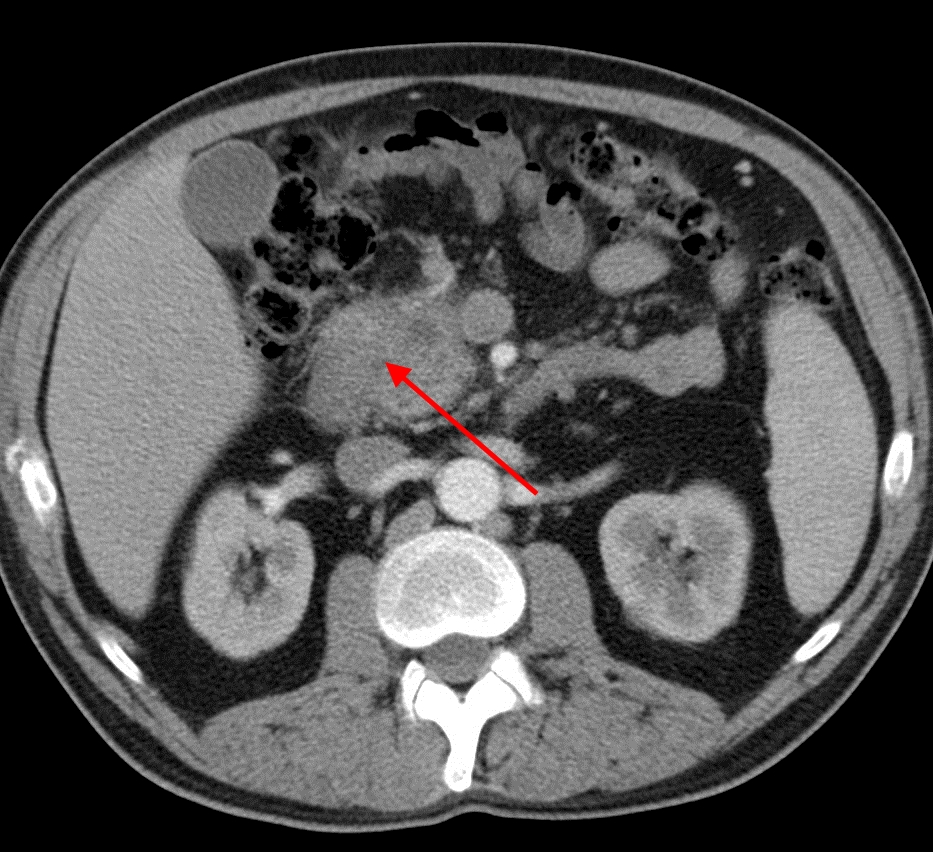

Для постановки диагноза врачу необходимо собрать анамнез жизни пациента, семейный анамнез, провести полный осмотр. Из лабораторных методов диагностики выполняют следующие: общий анализ крови, биохимический анализ крови, анализ на определение онкомаркеров, определение уровня тестостерона, анализ кала, общий анализ мочи. Из инструментальных методов доктор назначает УЗИ органов брюшной полости, КТ, МРТ, эндоскопическую ретроградную холангиопанкреатографию, биопсию.